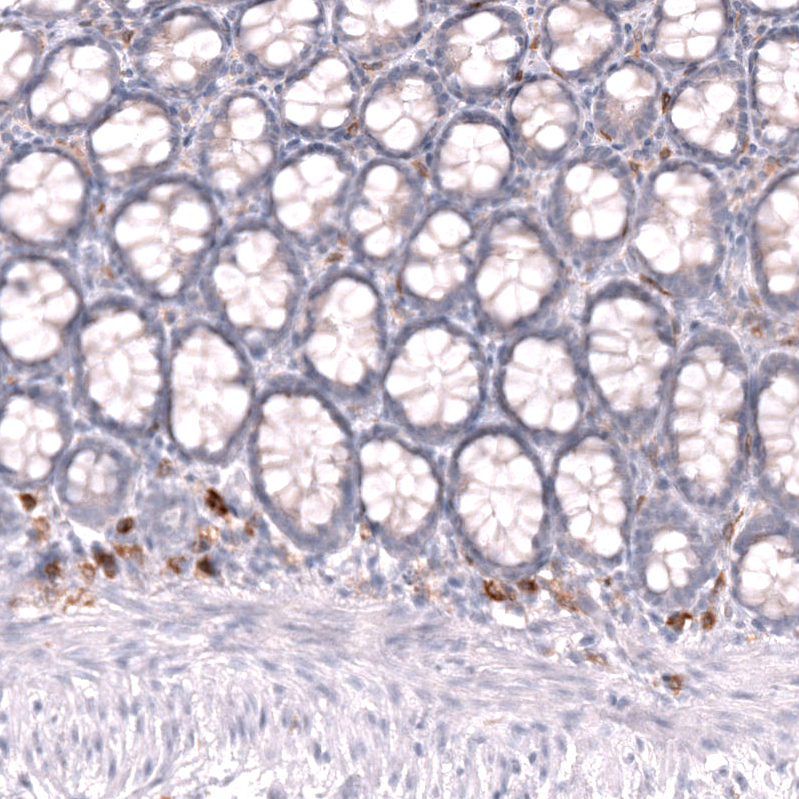

Immunohistochemistry analysis in human lymph node and placenta tissues using AMAb92049 antibody. Corresponding CLEC10A RNA-seq data are presented for the same tissues.